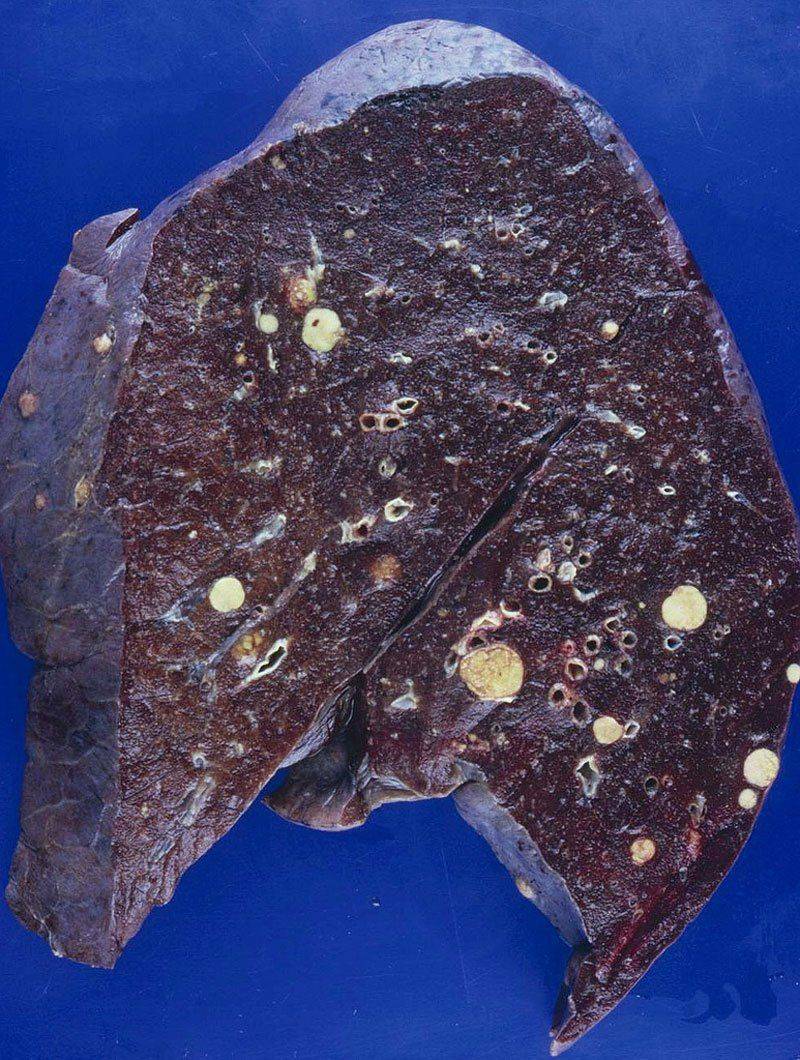

Фото раковой шишки на теле

Раковые шишки могут возникать не только на лице, но и на других частях тела. На фотографиях вы можете увидеть примеры раковых шишек на шее, руках, ногах и туловище. Обратите внимание на различные формы и размеры раковых шишек, а также на их внешний вид.